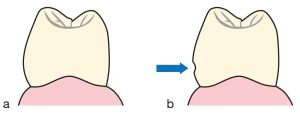

In the absence of anterior abutment teeth, the neighboring teeth may tip or shift into the space and the aesthetics of the tooth alignment may be compromised.

Even if the teeth are not drifted, a wide anterolateral undercut is formed in the lower part of the contour height (Fig. 10-25 a). The guide plane on this surface should also be parallel to the path of insertion (Figure 10-25 b). The tooth will be restored with a crown if the amount of preparation needed to make the modification is too great to remain inside the enamel borders.